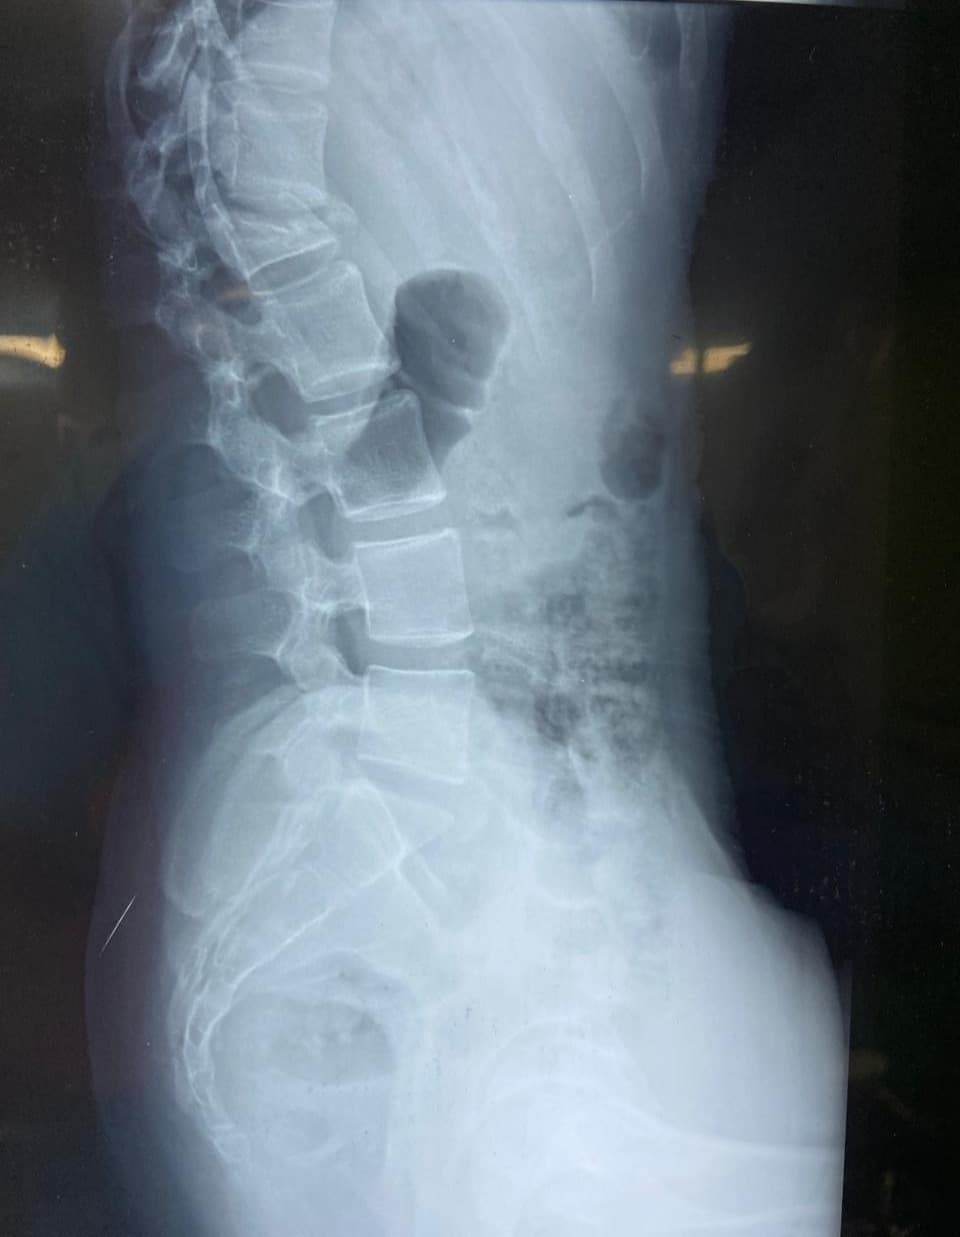

A 17-year-old girl was brought to us after a fall from the first floor of her house. She had sustained a severe injury to her spine and was unable to walk at the time of admission. X-rays and MRI revealed an L1 burst fracture with compression over the spinal cord. On clinical examination, she had paraparesis—weakness of both lower limbs—with significant difficulty in standing and moving. The family was deeply worried as her ability to walk again was uncertain. Given the severity of the spinal cord compression and the risk of permanent neurological loss, she was taken up for emergency posterior stabilization and decompression of the spinal cord